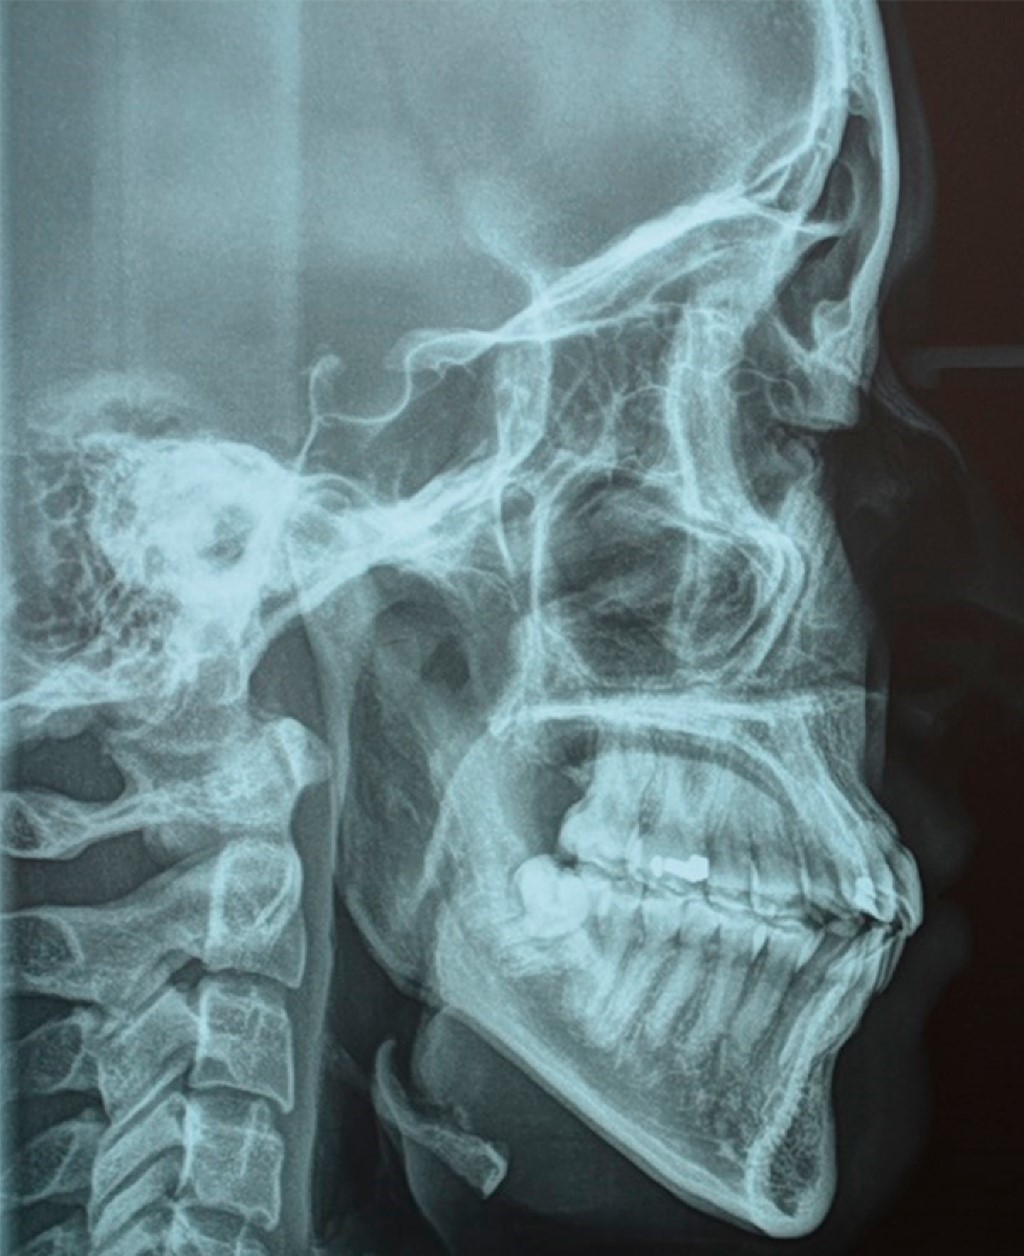

De acuerdo con la evaluación de los estudios radiográficos (Figuras 3 y 4), fotografías extra- e intraorales y datos cefalométricos (Tabla 1) se decide realizar tratamiento ortodóncico-quirúrgico y de esta manera cumplir con los objetivos planeados.

Paciente femenino de 21 años que se presenta en el Centro de Alta Especialidad "Dr. Rafael Lucio", cuyo motivo de consulta es "quiero cerrar la boca bien", no refiere alergias ni malos hábitos. Presenta un biotipo dolicofacial, cara ovalada, línea media facial no coincide con la línea media dental superior, sonrisa gingival de 8 mm y exposición de incisivo en reposo de 6 mm, con un perfil recto, deficiencia del tercio medio facial (Figura 1), mordida borde a borde en el sector anterior, mordida cruzada unilateral derecha posterior, un overjet de 0 mm, clase I canina bilateral, clase I molar derecha y III izquierda por la ausencia del OD 35, apiñamiento leve superior e inferior (Figura 2).

Figura 3

Figura 4